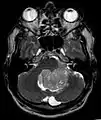

Épendymomes supratentoriels

Les épendymomes supratentoriels (SE) représentent entre 40% et 60% des tumeurs intracrâniennes. Localisées au niveau supratentoriel, ces tumeurs apparaissent comme des grosseurs peu homogènes, présentant des zones kystiques, des calcifications mais également des zones hémorragiques et nécrosées.

Aspect radiologique à l’IRM en séquence T1 après injection de Gadolinium d’un épendymome supratentoriel, caractérisé par une lésion bien délimitée du lobe frontal gauche avec prise de contraste hétérogène et des zones de nécrose.